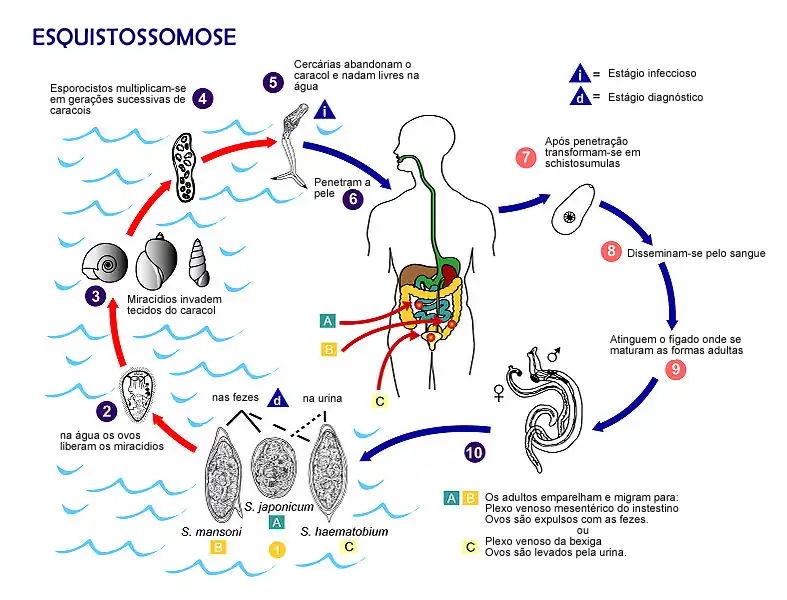

O ciclo da esquistossomose

A infecção humana pelo Schistosoma começa quando larvas aquáticas de vida livre, denominadas cercárias, entram em contato com a pele do hospedeiro. Estas cercárias são liberadas em grande número por caramujos de água doce, os hospedeiros intermediários do parasita, que foram previamente infectados por miracídios eclodidos de ovos eliminados por hospedeiros definitivos infectados. O contato com águas contaminadas por cercárias – seja em rios, lagos, canais de irrigação ou córregos – é o modo de transmissão da doença. A penetração da cercária na pele é um processo ativo e rápido, podendo ocorrer em questão de minutos após o contato. As cercárias são atraídas por secreções da pele e, ao encontrarem o hospedeiro, aderem à superfície cutânea e iniciam a invasão. Durante este processo, as cercárias perdem sua cauda bifurcada, uma estrutura utilizada para natação na água, e penetram através das camadas da epiderme.[33]

Uma vez no interior da pele, a larva, agora denominada esquistossômula, sofre uma série de transformações morfológicas e bioquímicas cruciais para sua sobrevivência e adaptação ao ambiente interno do hospedeiro. Uma das mudanças mais significativas é a perda do glicocálice externo, que é antigênico, e a formação de um novo revestimento superficial complexo, o tegumento heptalaminar. Este novo tegumento confere à esquistossômula resistência a mecanismos de defesa do hospedeiro, como o sistema complemento, e é fundamental para a evasão imune durante as fases subsequentes da infecção. Após a transformação na pele, as esquistossômulas iniciam uma complexa jornada migratória através dos tecidos do hospedeiro para alcançar seu destino final, o sistema vascular portal-hepático, onde ocorrerá a maturação sexual. Da derme, as esquistossômulas penetram em pequenos vasos sanguíneos (vênulas) ou linfáticos. O tempo necessário para alcançar a circulação varia entre as espécies.[33]

Uma vez na circulação sanguínea ou linfática periférica, as esquistossômulas são transportadas passivamente pelo fluxo sanguíneo. Elas atingem o lado direito do coração e são subsequentemente bombeadas, através da artéria pulmonar, para a microvasculatura dos pulmões. Os capilares pulmonares representam uma barreira física significativa devido ao seu pequeno diâmetro. Para atravessá-los, as jovens esquistossômulas devem se alongar e se deformar consideravelmente. A chegada e a permanência nos pulmões também variam temporalmente entre as espécies e podem ser influenciadas pelo tipo de hospedeiro definitivo. Após atravessarem os capilares pulmonares, as esquistossômulas entram nas veias pulmonares, retornam ao lado esquerdo do coração e são distribuídas pela circulação arterial sistêmica para diversos órgãos. A chegada ao sistema porta-hepático, o principal local de maturação, pode ocorrer por diferentes rotas.[34] As larvas que entram na artéria celíaca ou nas artérias mesentéricas superior ou inferior podem alcançar o fígado diretamente através da artéria hepática ou, mais comumente, atravessando a vasculatura capilar de órgãos como estômago, intestino delgado, baço ou pâncreas, e então entrando na veia porta hepática. Uma vez no fígado, as esquistossômulas são predominantemente encontradas nos ramos intra-hepáticos da veia porta e parecem ficar retidas nesse sistema, incapazes de atravessar os sinusoides hepáticos para retornar à circulação sistêmica. Esta fase pulmonar e de migração sistêmica é crítica, pois o parasita está exposto a respostas imunes do hospedeiro, e a passagem pelos pulmões é um evento obrigatório para o desenvolvimento subsequente.[33]

Ao alcançarem o ambiente vascular intra-hepático, principalmente os ramos da veia porta, as esquistossômulas encontram um nicho rico em nutrientes, onde iniciam um período de intenso crescimento e desenvolvimento. Alimentando-se de componentes sanguíneos do hospedeiro, como eritrócitos, e utilizando glicose e ácidos graxos para seu metabolismo energético e para a produção de ovos , as larvas amadurecem sexualmente, transformando-se em vermes adultos machos e fêmeas. Este processo de maturação, desde a penetração na pele até a capacidade de produzir ovos, leva aproximadamente de 5 a 7 semanas. Em S. mansoni, por exemplo, as esquistossômulas podem dobrar de peso a cada 2,3 dias durante as duas primeiras semanas no fígado. Após o acasalamento, os casais de vermes iniciam uma segunda migração, desta vez do fígado para seus sítios preferenciais de oviposição no sistema vascular.[33] Notavelmente, esta migração ocorre, em grande parte, contra o fluxo sanguíneo predominante no sistema portal, que é direcionado para o fígado.Após atingirem a maturidade sexual e se estabelecerem nos sítios vasculares preferenciais, as fêmeas de Schistosoma iniciam a oviposição. São precisamente estes ovos retidos nos tecidos do hospedeiro que constituem o principal estímulo para a resposta inflamatória crônica e a subsequente patologia associada à esquistossomose.[35] Cada ovo aprisionado induz a formação de um granuloma, uma reação inflamatória celular organizada que, embora possa ter um papel protetor inicial, a longo prazo leva à fibrose tecidual, disfunção orgânica e às manifestações clínicas crônicas da doença.[36]